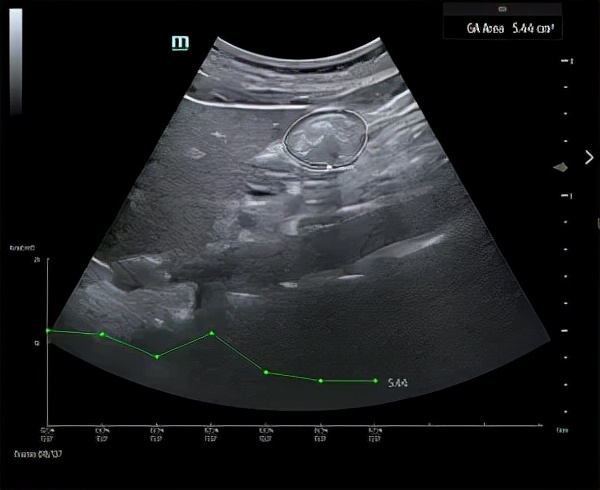

迈瑞的 TE9 是第一台具有自动 GA 功能的床旁超声设备(照片由迈瑞提供)

相较于TE7来说,带有首个Auto GA(胃窦)复杂评估功能的TE9超声系统就更上一层楼了。它可通过自动识别胃窦的边缘,胃的较小远端部分,并通过单次屏幕点击测量其面积,帮助临床医生评估胃内容物。该信息有望帮助确定哪些外科手术适合个别患者。

除了 Auto GA 之外,TE9 还配备了 21.5 英寸的大型高清触摸屏以及一流的成像和换能器技术,可实现快速准确的诊断。它还提供智能 IVC 等自动化功能,帮助临床医生评估和收集患者在床边、手术室或移动时的可重复测量值。